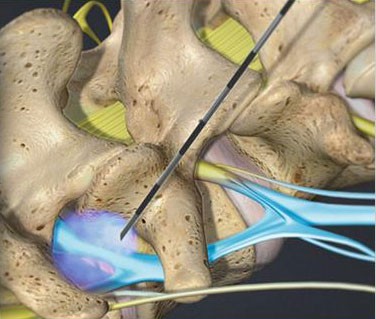

- Caudal Steroid Injection

- Facet Joint Injections

- Joint Steroid Injection

- Lumbar Epidural Steroid Injection

- Medial Branch Block